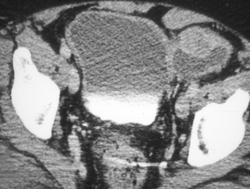

Bilateral Renal Abscesses